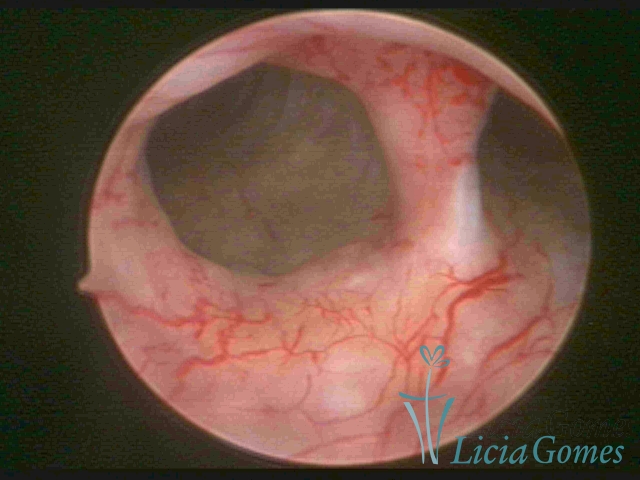

Bicornuate uterus

Malformation in which there is the lack of the flat portion of uterine fundus due to the lack of fusion on the proximal portion of paramesonephric ducts. The uterine fundus has two narrowed spaces in a divergent oblique angulation. It may be complete, from the fundus to the cervix; or partial, completely dividing the uterine cavity.

The tilted uterus which presents the most difficult hysteroscopic diagnosis occurs when there is only a small indentation of the uterine fundus.